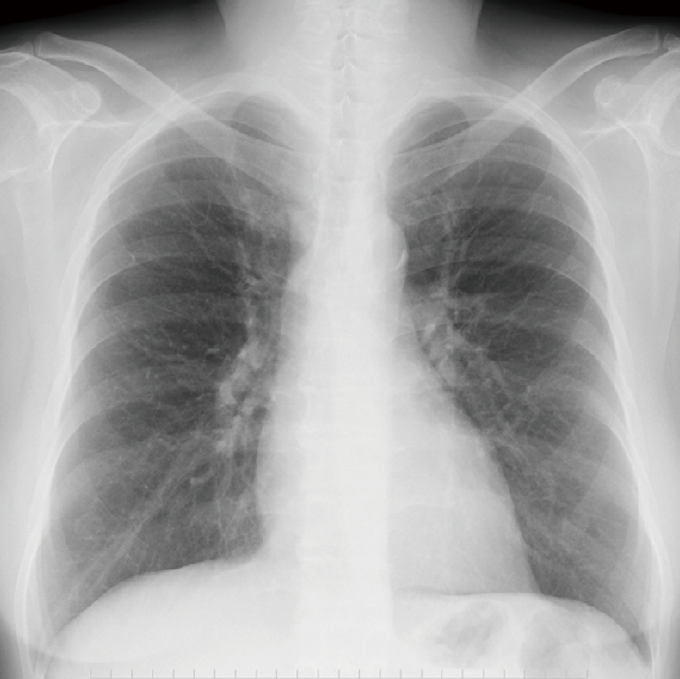

読む順番に決まりはないが、自分のなかで読む順番を決めておくと見落とすことが少なくなる(写真3)。

写真3読む順番を決めておく

6肺野

左右での透過性の違いがあるか、上から下へ向かい左右を比較していく。

後述するシルエットサイン、コンソリデーション、エアブロンコグラムは存在するか、血管影は末梢まで追うことができるか。